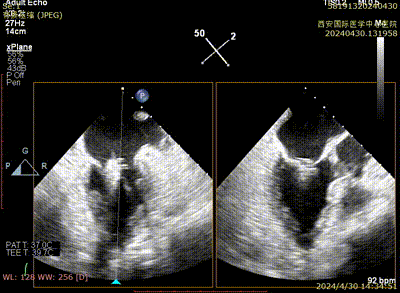

Case 2影像资料

房间隔穿刺

导引鞘系统植入

二尖瓣夹系统瓣上调整

二尖瓣夹系统进入左室

二尖瓣夹捕获瓣叶

二尖瓣夹夹闭

术后二尖瓣反流评估

术后结果